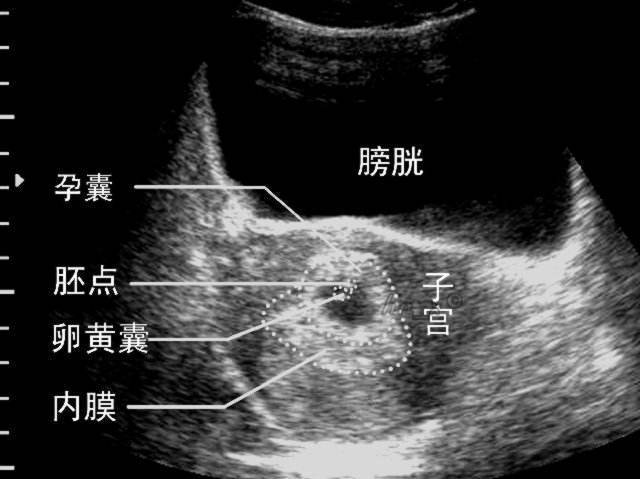

妊娠囊 360百科

怀孕多久才照到孕囊 问起网 婴幼儿百科全书

教窍 如何通过超声波识别早孕胶囊 假孕胶囊 手机备用网址 Bet体育app 365bet体育最新网址